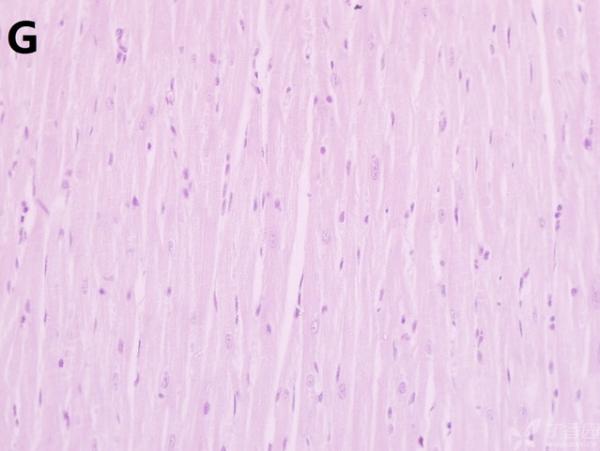

ÎÒ½«Ã¿¸ö×éÖ¯ÅÄÁË3¸öÊÓÒ°£¬ÒÔ±ã×ۺϷÖÎö£¬Âé·³¸÷λ°ïÎÒ°ÑA¡¢B¡¢C¡¢D¡¢E¡¢F¡¢GµÄËðÉË´óСÅŸö˳Ðò ÔÙ°ÑA¡¢B¡¢C¡¢H¡¢I¡¢JËðÉ˵ÄÑÏÖØ³Ì¶ÈÅŸöÐò¡£¸ÃÎÊÌâÒ²ÔÚ¶¡ÏãÔ°ÉÏÇóÖúÁË£¬Á´½Óhttp://www.dxy.cn/bbs/topic/23986562 A1.jpg A2.jpg A3.jpg B1.jpg B2.jpg B3.jpg C1.jpg C2.jpg C3.jpg D1.jpg D2.jpg D3.jpg E.jpg F1.jpg F2.jpg F3.jpg G1.jpg G2.jpg G3.jpg H1.jpg H2.jpg I.jpg I2.jpg I3.jpg J.jpg J2.jpg J3.jpg [ Last edited by ÀëÈËÏæÑÅÀá on 2012-10-9 at 21:11 ] |